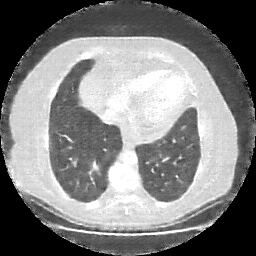

Original NATIVE CT scan (input)

Lung window (WL -600, WW 1500 β†’ Low βˆ’1350, High +150)

Reconstructed NATIVE CT scan (cycle consistency)

Original VENOUS CT scan

Generated VENOUS CT scan (A→B translation)